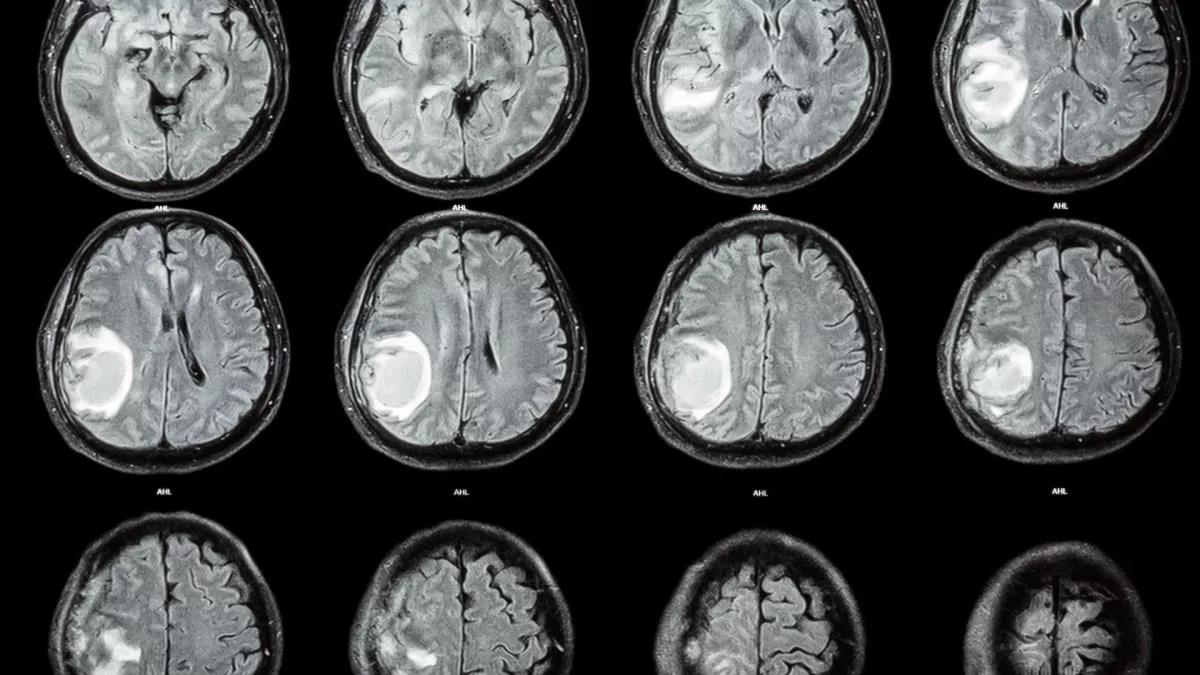

Hình ảnh CT scan đầu của đứa trẻ 1 tuổi - Ảnh: NEUROLOGY

Nghiên cứu dẫn đầu bởi bác sĩ thần kinh học Zongze Li từ Phòng thí nghiệm Peng Cheng (Thâm Quyến - Trung Quốc) cho biết bệnh nhi giấu tên được kiểm tra bằng CT scan khi có những dấu hiệu chậm phát triển thần kinh vận động, đầu to lên bất thường, ứ dịch.

Các hình ảnh cho thấy một khối u lạ xuất hiện trong não đứa trẻ, được xác định là một bào thai vì có cột sống và hai chương chân, cũng như cho thấy thai nhi đó là một thai bị dị tật nứt đốt sống. Thai nhi cũng đã phát triển một chồi chi trên và cấu trúc giống ngón tay.